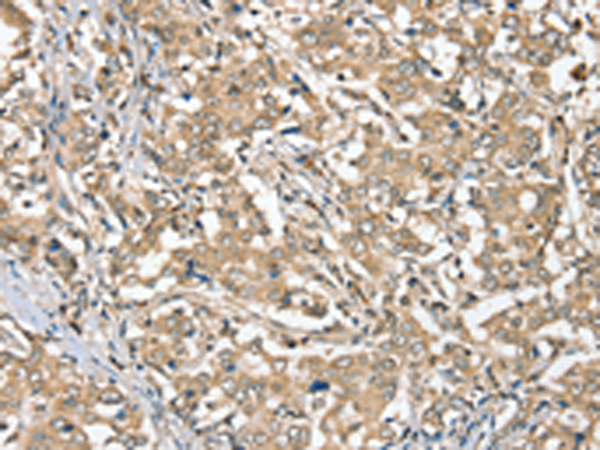

分类: 科研抗体货号: P12176别名: MCT3; REMP应用: WB,IHC反应种属: Human